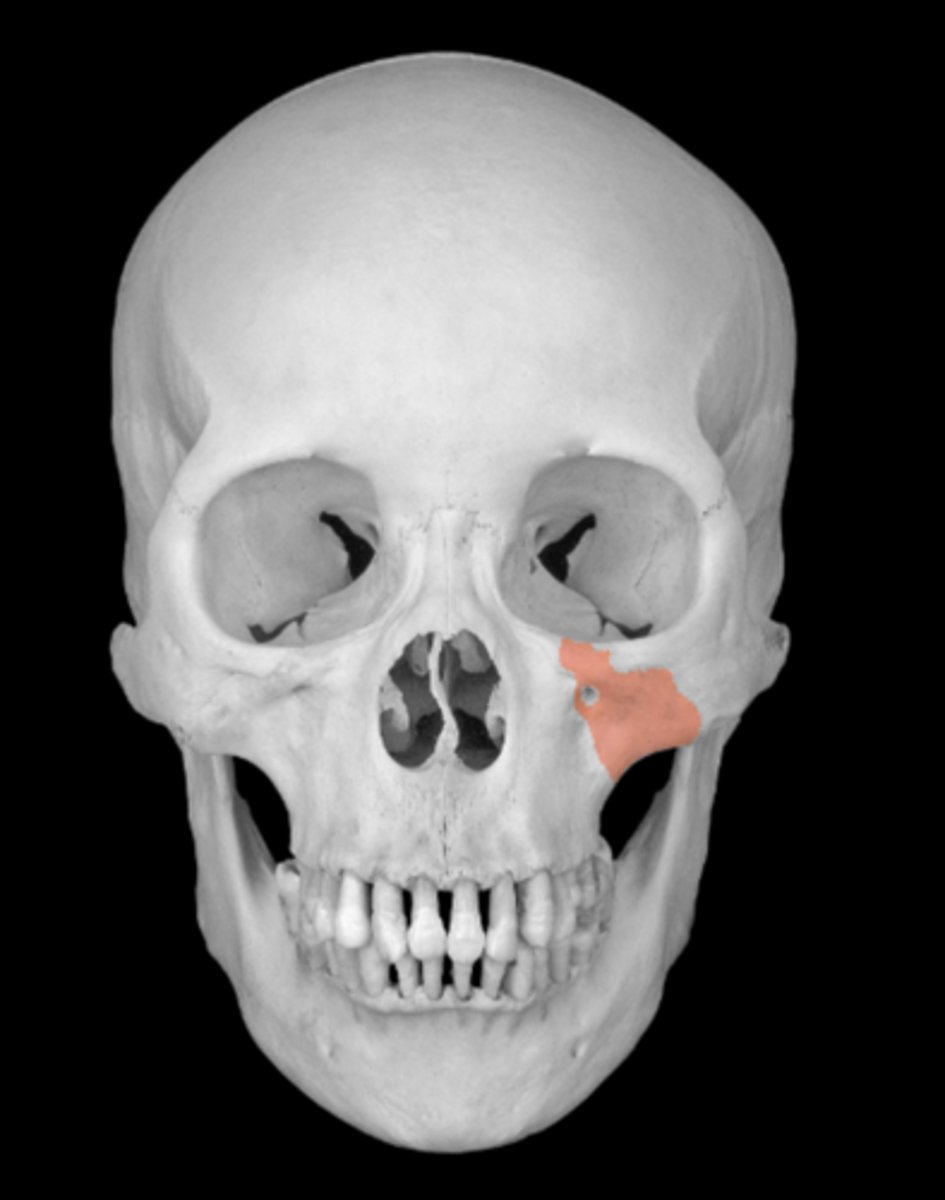

maxilla bone

zygomatic process of maxillae

infraorbital foramen of maxilla